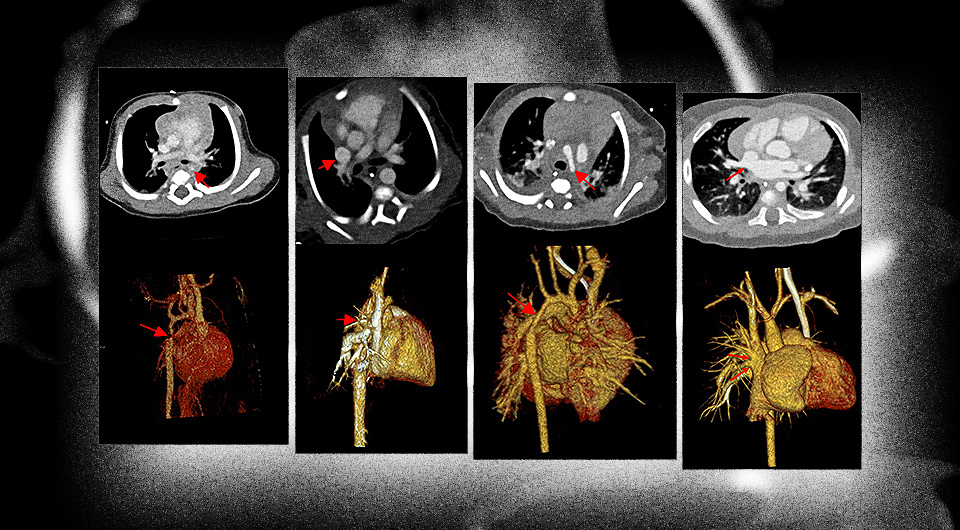

Компьютерная томография (КТ) с подсчетом фотонов показала более четкие и контрастные изображения у детей с врожденными пороками сердца, нежели КТ с двумя источниками излучения. Немецкие радиологи в статье для журнала Radiology, отмечают, что оба метода имеют схожую дозу облучения.

Примерно у процента новорожденных детей наблюдаются врожденные пороки сердца разной степени тяжести. У четверти таких детей дефект будет критическим и потребует хирургической коррекции в течение первого месяца жизни. Хотя порок развития можно обнаружить с помощью ультразвукового исследования на скринингах во время беременности, порой этого метода бывает недостаточно для полноценной диагностики врожденного дефекта сердца.